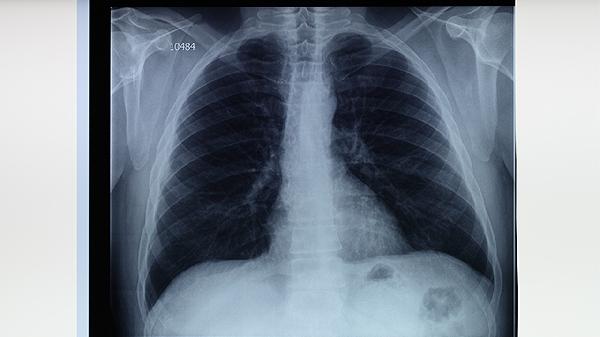

肺结核可以用中医治疗,但需与西医抗结核药物联合使用。肺结核是由结核分枝杆菌引起的慢性传染病,中医治疗主要作为辅助手段,有助于缓解症状、增强体质。常用方法包括中药调理、针灸等,但必须遵医嘱规范使用异烟肼片、利福平胶囊等抗结核药物。

中医认为肺结核属于肺痨范畴,多因正气不足、痨虫侵袭所致。治疗以滋阴润肺、补气健脾为主,常用百合固金汤、月华丸等方剂。中药成分如百部、白及、黄精等具有抑菌作用,可辅助抑制结核杆菌。针灸选取肺俞、膏肓等穴位能改善咳嗽盗汗。部分中成药如抗痨胶囊、肺泰胶囊也可配合使用。

单纯中医治疗无法彻底杀灭结核杆菌,擅自停用西药可能导致耐药性。活动期肺结核需坚持服用利福平胶囊、吡嗪酰胺片等药物6个月以上。中药调理期间应定期复查肝功能,避免何首乌等肝毒性药材长期使用。咯血患者慎用活血化瘀类中药,阴虚火旺者忌用人参等温补药。

肺结核患者需保持居室通风,饮食宜高蛋白、高维生素。适当食用银耳、山药、梨等润肺食材,避免辛辣刺激。中医治疗期间仍需隔离痰菌阳性者,规范处理痰液。若出现药物性肝损伤或过敏反应,应立即停用中药并就医。中西医结合治疗需在传染病专科医生指导下进行。